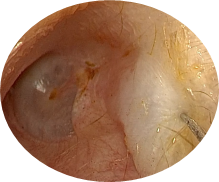

Vue endoscopique de du conduit auditif externe :

- Tympan

- Conduit auditif externe